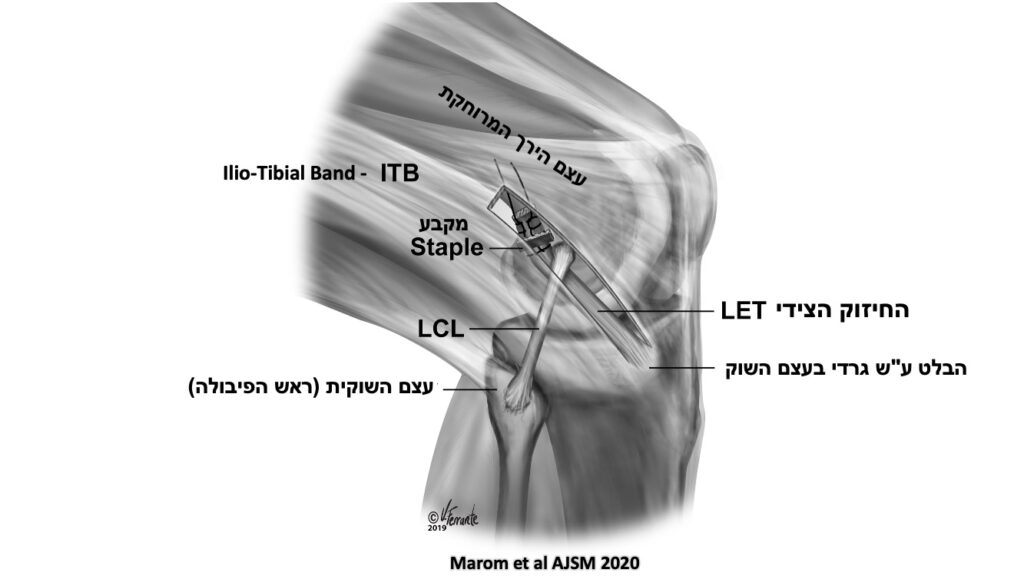

אחת מהפרוצדרות הניתוחיות המקובלות ביותר כיום לחיזוק צידי היא Lateral Extra-articular ITB Tenodesis (LET) בה מפרידים חלק מה-(ITB) Ilio-Tibial Band (רצועת ירך-שוק הצידית) ומקבעים אותו לעצם הירך המרוחקת. למרות שפרוצדורה זו הפכה שכיחה בעת האחרונה, עדיין לא ברורות לחלוטין כל ההשפעות שלה על מפרק הברך בדגש על עומסים/לחצים גבוהים יותר מהנורמה שעלולים להתפתח במדור הצידי של הברך (Lateral compartment).

בעבודה זו נבדקה ההשפעה של הניתוח המשולב שכולל ביצוע חיזוק צידי (LET) בשילוב עם שחזור רצועה צולבת קדמית על העומסים והלחצים במדור הצידי של הברך בזמן תנועות סיבוביות של הברך המחקות את מנגנון הפציעה של הרצועה הצולבת הקדמית (Pivoting maneuvers).